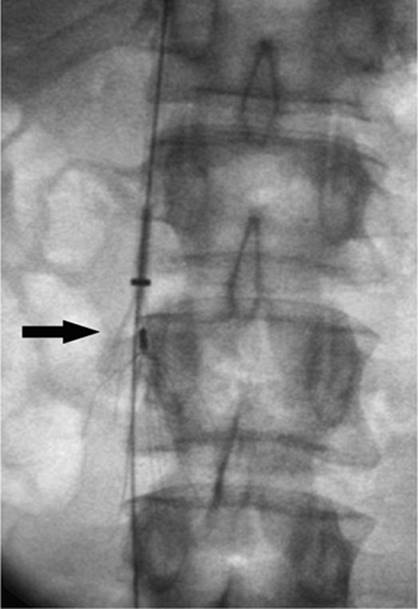

If the femoral routes are unable to be used, the next appropriate site would be a translumbar access. This involves puncturing the inferior vena cava directly from a posterior approach over the right iliac crest below the level of the renal veins. Once accessed, the tract is dilated to accommodate the catheter, which is directed into the superior portion of the inferior vena cava. This procedure definitely requires fluoroscopic guidance and carries increased risk of procedure-related complications.

One additional site that should be mentioned is the transhepatic approach. When the IVC is occluded and all other sites have been exhausted, vascular access can be achieved by puncturing the intrahepatic portion of the hepatic vein from a right upper quadrant approach, much as if performing a biliary drainage catheter placement. However, instead of aiming for the bile ducts, the hepatic vein is cannulated and the tract dilated to accommodate the appropriate catheter, which is positioned with its tip in the right atrium (Figs. 35.33 and 35.34).